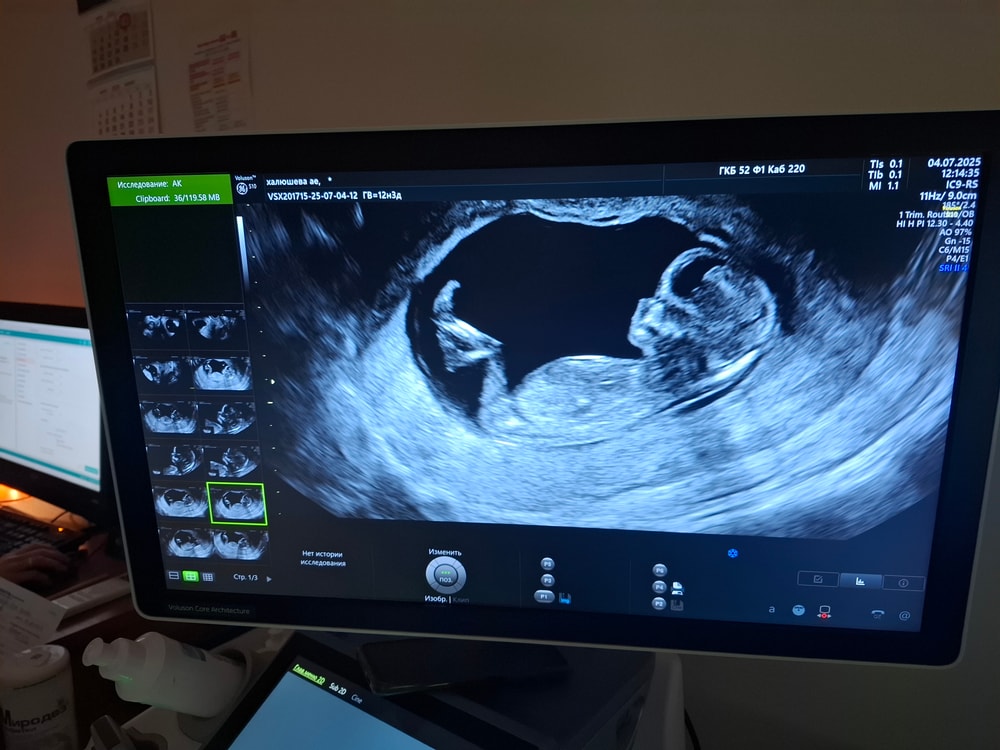

Полового бугорка не видно, но по профилю лица больше на девочку похожа, стройненькая и длиноногая☺️

Какое фото четкое 👍🏻 Полового бугорка нет на нем.

Анна, тут не видно полового бугорка

Анна, не знаю почему, кажется, как будто на девочку похожа)) Если по делу, тут на фото даже полового бугорка не видно, даже рассудить не о чем, а жаль..Не расстраивайтесь, что не сказали пол, можете сходить на УЗИ в платную, хотя бы через неделю и скорее всего скажут! Мне на 1-ом скрининге сказали пол, но была очень неприятная врач, я из нее клещами вытянула, срок был как ваш, и то, она меня язвительными комментариями провожала, мол «с ума посходили мамаши все им сразу» 😕